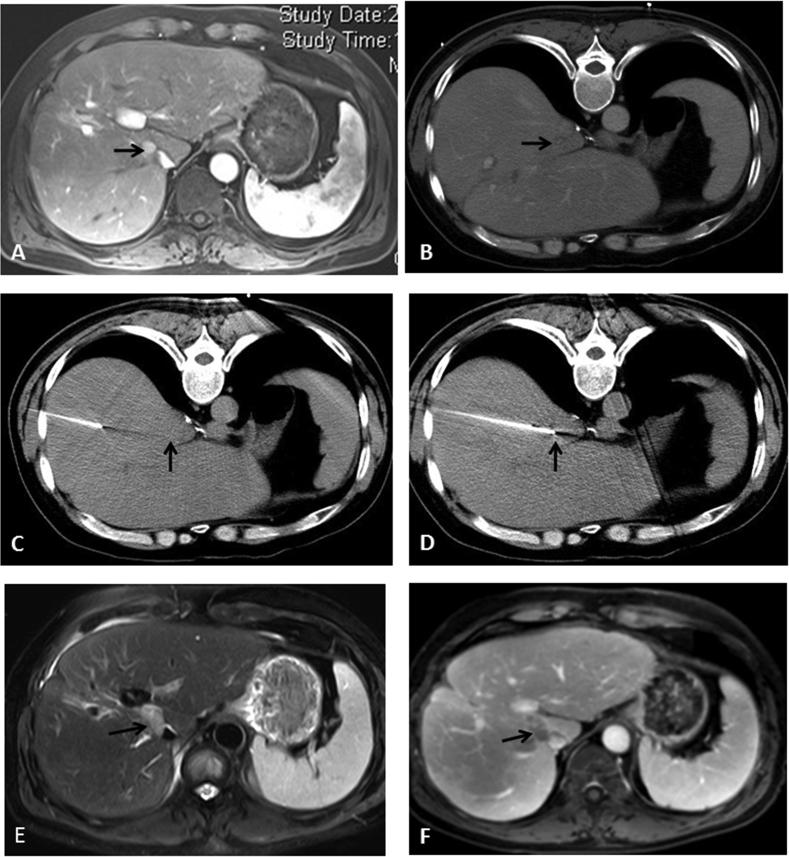

Computed tomography-guided radiofrequency ablation of the retained iodized oil after simultaneous combination with transarterial embolization in small recurrent or residual hepatocellular carcinoma.

To assess the clinical efficacy and safety of transarterial embolization (TAE) in simultaneous combination with computed tomography (CT)-guided radiofrequency ablation (RFA) for recurrent or residual hepatocellular carcinoma (HCC), and to determine the risk factors influencing local tumor progression following this procedure.

One hundred eighteen patients with recurrent or residual HCC (tumor size, 10-30 ​mm) underwent RFA. During the 19-month follow-up, 59 patients received RFA only (RFA group), and the remaining 59 received RFA immediately after TAE (TAE ​+ ​RFA group). All patients were followed up to observe the short-term therapeutic effects and complications. The cumulative local tumor progression rates in both groups were calculated using unpaired Student's t tests and the Kaplan-Meier method.

The rate of major complications was 5.08% in the TAE ​+ ​RFA group and 3.39% in the RFA group. The overall response rate was 96.61% in the TAE ​+ ​RFA group and 79.66% in the RFA group ( ​= ​0.008). The disease control rate was significantly higher in the TAE ​+ ​RFA group than in the RFA group (94.92% vs. 79.66%,  ​= ​0.024). The median time to local tumor progression was 4.8 months in the RFA group and 9.6 months in the TAE ​+ ​RFA group. The cumulative local tumor progression rate at 1 year was 10.60% in the RFA group and 23.60% in the TAE ​+ ​RFA group ( ​= ​0.016).

TAE in simultaneous combination with CT-guided RFA was effective and safe against recurrent or residual HCC. Local tumor progression can be minimized by the complete ablation of targeted iodized oil deposits after simultaneous TAE.